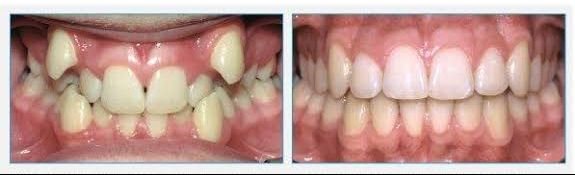

MOST POPULAR TREATMENTS

What we offer